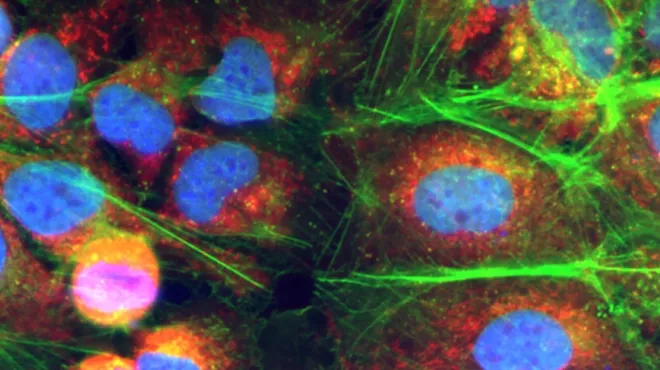

Celle- og genterapier bygger på grundig forskning, der bygger på mange årtiers videnskabelige fremskridt. De centrale redskaber og teknologier er blevet afprøvet og raffineret af utallige eksperter – først i laboratoriet og sidenhen i klinikken. Ved celleterapi dyrkes eller modificeres cellerne uden for kroppen, før de indsprøjtes i patienten, hvor de udvikler sig til et "levende lægemiddel". Ved genterapi udskiftes, inaktiveres eller indføres generne i celler – enten uden for eller inde i kroppen – for at behandle en sygdom. Nogle behandlinger kvalificerer sig som både celle- og genterapier.

Den enkelte celle- og genterapi udvikles på grundlag af detaljeret information om årsagerne til en patients sygdom. Den behandler en tilstand eller sygdom ved kilden ved på genniveau at reparere eller forbedre celler. Hos Novartis samarbejder vi inden for celle- og genterapi for at bringe denne revolutionerende behandlingsform til patienter med en lang række sygdomme, herunder genetiske sygdomme og visse livstruende kræftformer.

Alle disse behandlinger lever op til betegnelsen præcisionsmedicin – en term der vandt udbredelse, første gang videnskaben fastslog DNA-sekvensen i hele det menneskelige genom. Den gang drømte forskere om at udnytte information om hvert enkelt menneskes gener til at skræddersy behandlinger til patienter og dermed fundamentalt forandre lægevidenskaben. Celle- og genteknologi bringer os tættere på dette ambitiøse mål.